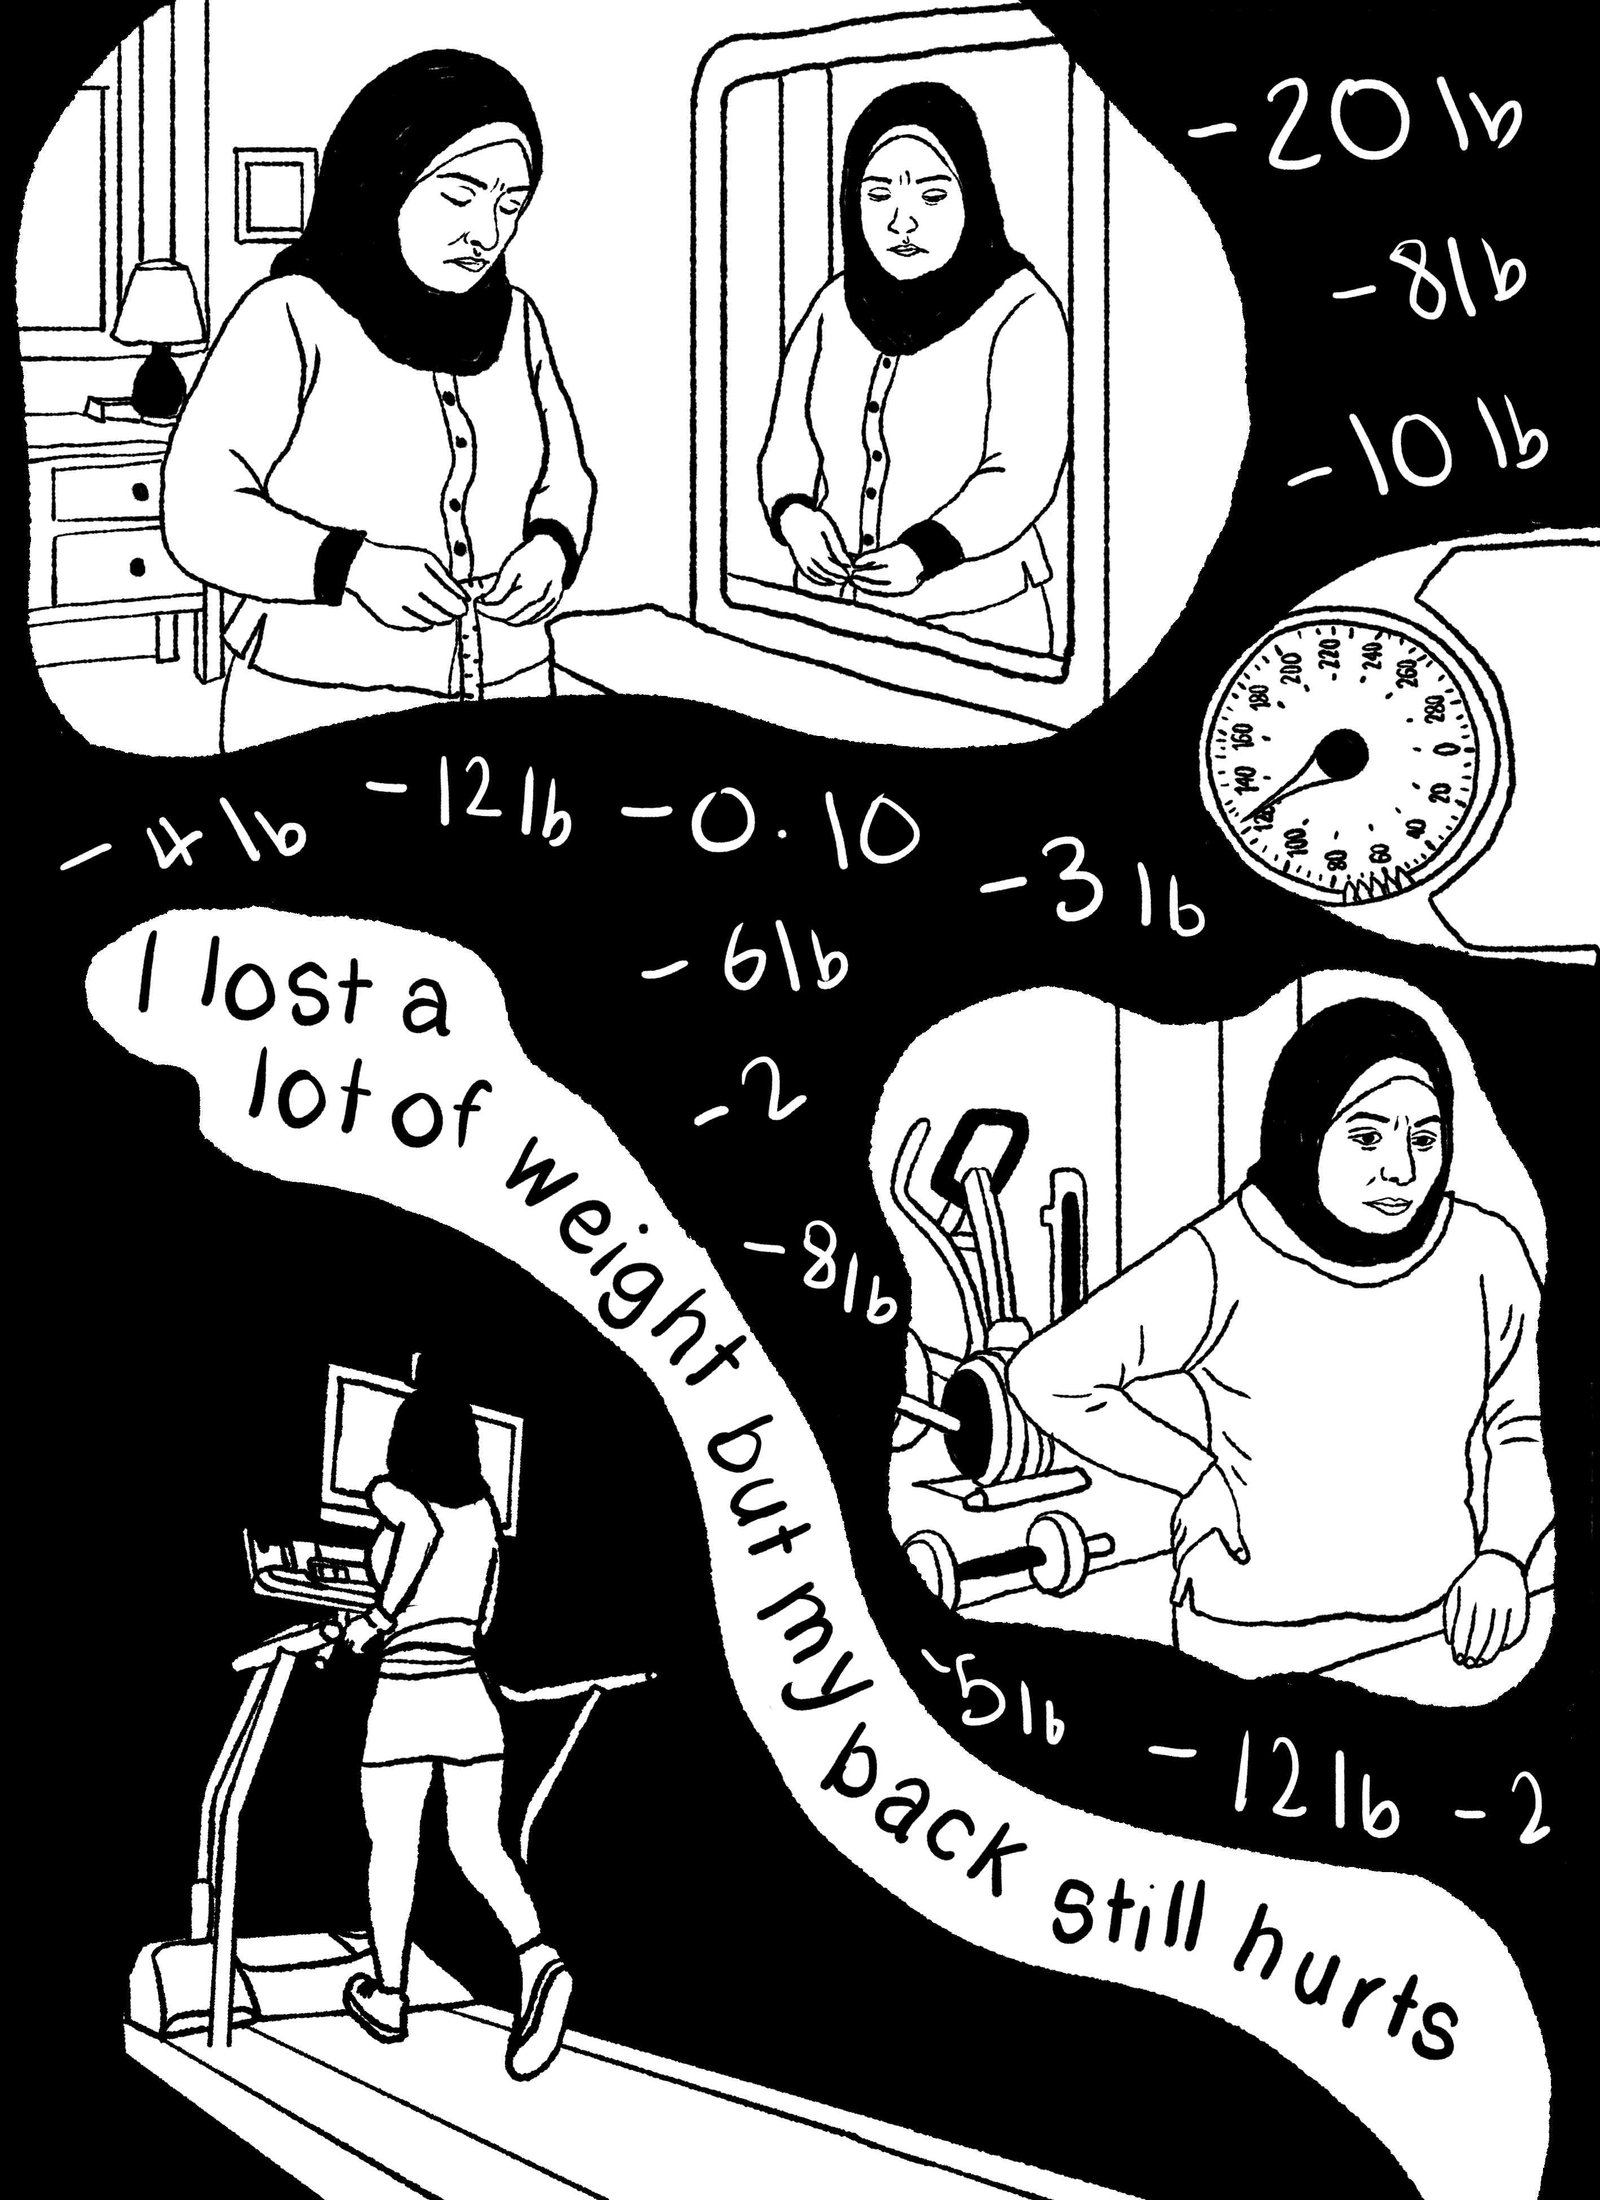

Blue Filter - first

The P.O.V of the female patient, the reality of what is happening.